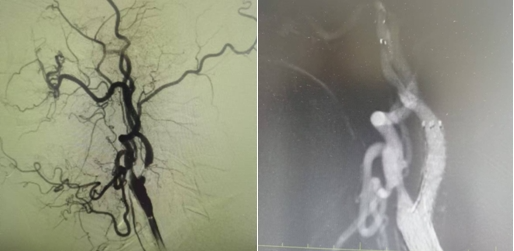

1個月前姜大爺(化名)反復(fù)出現(xiàn)右側(cè)肢體抽搐癥狀,碾轉(zhuǎn)當(dāng)?shù)囟嗉裔t(yī)院治療,效果不理想,嚴(yán)重影響日常生活,在家人的陪同下來到國文醫(yī)院神經(jīng)介入科。入院后給予行頭MRI彌散+頸部MRA提示:左側(cè)大腦半球分水嶺性腦梗死,左側(cè)頸內(nèi)動脈起始處重度狹窄,給予行DSA提示:左側(cè)頸內(nèi)動脈起始處重度狹窄至閉塞前改變。

丁金明主任指出:患者反復(fù)抽搐原來是血管狹窄惹得禍,跟患者家屬交代病情后,患者家屬要求血管內(nèi)介入治療,在導(dǎo)管室傾力配合下,順利完成“左側(cè)頸內(nèi)動脈起始處重度狹窄支架植入術(shù)”,術(shù)后患者未再出現(xiàn)抽搐癥狀,術(shù)后在醫(yī)護(hù)人員的精心治療和悉心護(hù)理下,患者恢復(fù)良好即將出院。